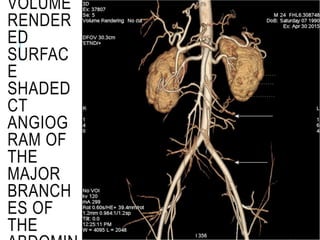

VOLUME

RENDER

ED

SURFAC

E

SHADED

CT

ANGIOG

RAM OF

THE

MAJOR

BRANCH

ES OF

CT ANGIOGRAM